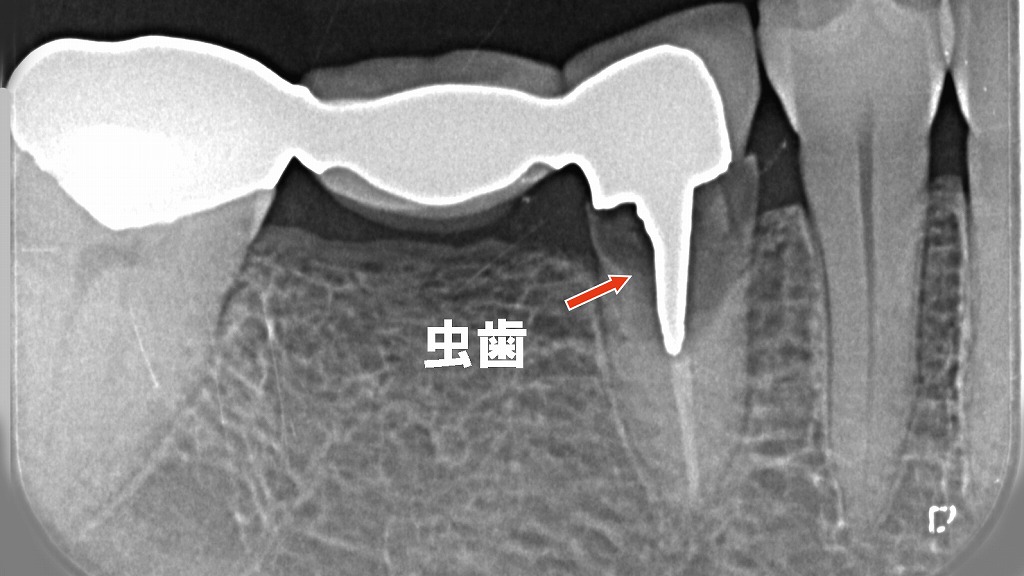

このレントゲン画像は、下顎の5番・6番・7番にかけて装着されたブリッジを示しています。以下のような特徴と臨床的な問題点があります。

- **下顎の7番(左の支台歯)と5番(右の支台歯)**がブリッジの支えとなり、6番相当部には人工歯(ポンティック)が入っています。

- 5番には金属のポストが装着されています。

⚠️ 5番の問題点:ポスト周囲の虫歯

- 赤い矢印の位置に見られるように、5番支台歯の根管内ポスト周囲に黒っぽい透過像があります。

- これは**二次う蝕(再発虫歯)**の所見であり、セメントの溶解や接着不良から細菌が侵入した結果です。

- 抜歯が必要になると判断しました。

💨 口臭・銀歯のにおいの原因

- ブリッジの下や接着面のすき間にプラークや食べかすが残存しやすく、そこに細菌が繁殖して**口臭(メタリック臭・腐敗臭)**が発生することがあります。

- 金属クラウン(特に保険の銀合金)は、長期使用で腐食や溶出が起こり、においの原因になることもあります。

🧱 セメント接着の劣化

- 長年の使用でセメントが溶解・劣化し、微小な隙間が生じると、そこから唾液・細菌が侵入して虫歯や炎症を引き起こします。

- ブリッジ全体の動揺や、噛むときの違和感・しみる症状が出る場合もあります。

🔍 治療の方向性

- ブリッジを一度除去して虫歯の範囲を確認しますが、再治療の余地が少ない状態です。

🦴 抜歯後の治療選択肢

- インプラント

- 失った5番部位にチタン製インプラントを埋入。

- 隣在歯を削らずに独立した人工歯として回復できる。

- 咬合力が強く、長期的に安定。

- 再ブリッジ

- 4番と7番を新たに支台歯にしてブリッジを再製作。

- ただし、健康な4番を削る必要があるため慎重な判断が必要。

- 部分入れ歯

- 費用を抑えたい場合の選択肢。

- 金属バネの見た目や違和感がデメリット。